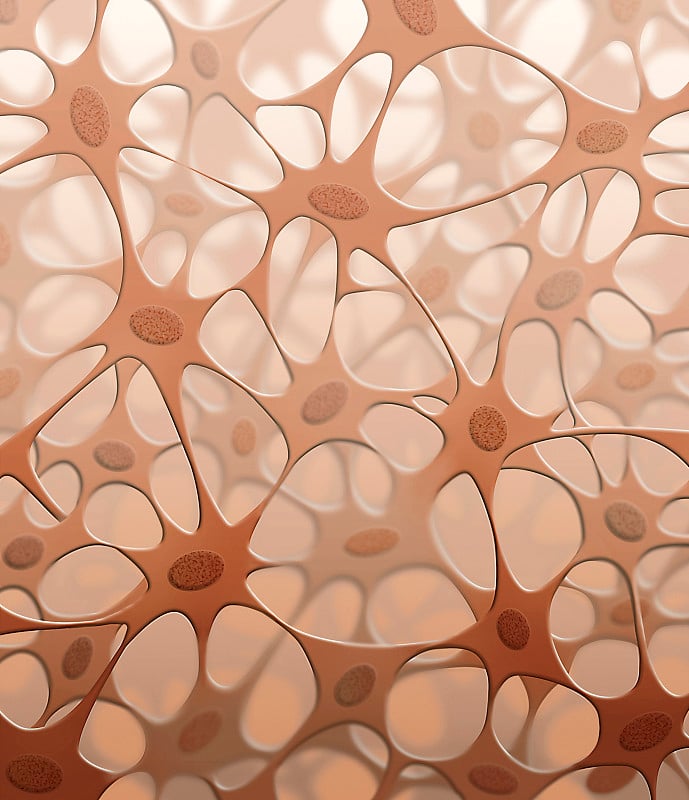

结缔组织详情

JPG